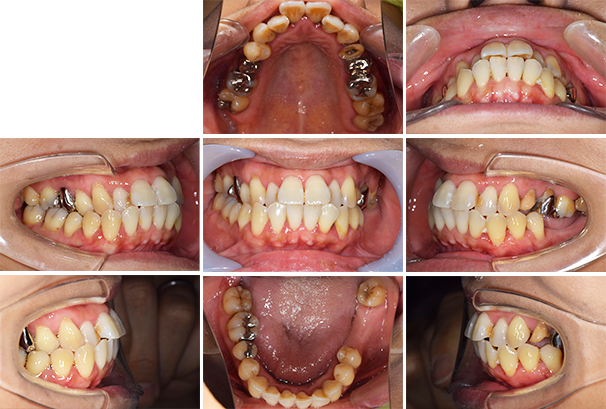

【担当医師所見】

歯周病の治療の必要性

ブラッシング方法の教授

左下奥歯は親知らずが原因でクラウン(かぶせ物)の下まで虫歯になっています。 またその手前の歯は根中央部に大きな透過像(黒い像)が見られます。クラウン除去後、マイクロスコープ下で確認したところ中央部は亀裂が入り保存不可能な状態になっており抜歯となりました。

また右上6番にも大きな透過像があり虫歯となっていることがわかります。

右上の銀歯の下にあった虫歯は大きかったものの歯の神経を残すことがなんとかできたので部分的なセラミックのつめ物(セラミックインレー)での治療となりました。

また反対側の奥歯も古くなっており、将来性を考えセラミックへ変更しています。